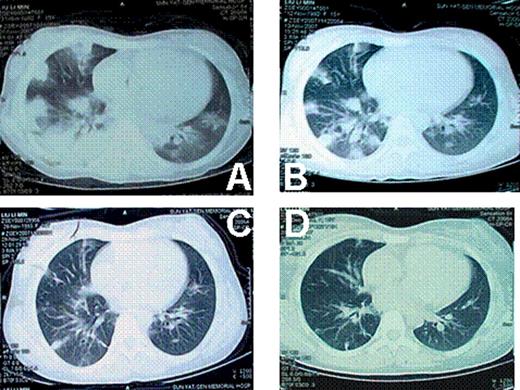

At the onset of the pulmonary diseases, anti-GVHD drugs (Including prednisone, CsA) were already withdrawn for both cases. There was no GVHD progression after withdrawal of the anti-GVHD drugs. Both cases had fever, ranging from 38 to 39 centigrade. Patients were short of breath. Oxygen inhalation was needed. Case 1 was in severe hypoxia. The oxygen saturation was down to 70%∼80% at the peak severity. Neither of the 2 cases was in need of mechanical ventilation. CT images showed that these 2 cases had similar lung injuries (Fig 1 and Fig 2). Tissue biopsy revealed that different pathogens were involved in these 2 cases, although they had identical disease history, similar duration after transplantation, same clinical symptoms and signs, even similar CT images. The histological findings of lung biopsies showed that the pathogen for case 1 was aspergillums, whereas that of case 2 was tubercle bacillus. Both cases responded well to the specific treatment, respectively. Patients are now in disease-free state.

Both tuberculosis and fungus infection could show diffused foci on CT image. The diffused lesions of tuberculosis tend to fuse, whereas little cavities were more frequently seen in fungus infections. After treatment, the lesions of fungus were much easier to be clear than tuberculosis. Diagnostic treatment might be used to distinguish these 2 diseases if biopsy cannot be performed or pathogen culture is negative.

lung CT of case 1. A: when the pulmonary infection began; B: 2 weeks later; C: 4 weeks later; D: 8 weeks later.